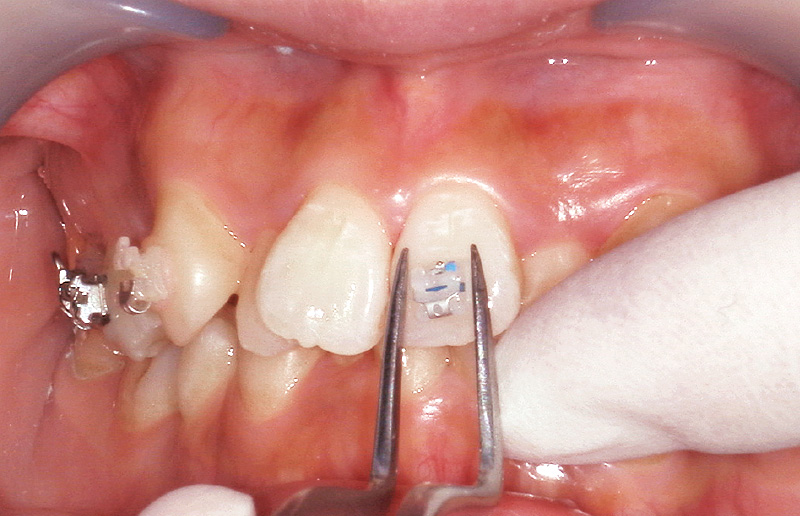

使用方法は「スーパーボンド」と同様であるが、「ボンドフィルSBⅡ」の特徴的な点は粉液比にあり、「キャタリストV」1滴に対し液材3滴の割合で使用する(図8)。被着体ごとの適切な前処理を行った後、筆積法を用いてブラケットを被着面に圧接し、はみ出した余剰レジンを除去する。次に光照射を行い、最低3分以上経過後に十分な重合を確認してからワイヤーを装着する(図9~12)。ただし、「スーパーボンド」および「ボンドフィルSBⅡ」は最終的な硬化が完了するまでに24時間を要するとされている。特にジルコニア冠やCAD/CAMレジン冠などはブラケット脱離が多いことが報告されているため、接着強さおよび重合率が最大になる24時間経過後にワイヤーを装着することで、ブラケット脱離のリスクを軽減できると考えている。

![[写真] 慎重にブラケットを歯のFAポイントに位置付ける](/academic/dentalmagazine/wp-content/uploads/sites/2/2025/11/195-13_photo09.jpg)

図9 慎重にブラケットを歯のFAポイントに位置付ける。 -

![[写真] 探針で位置を微調整後、圧接](/academic/dentalmagazine/wp-content/uploads/sites/2/2025/11/195-13_photo10.jpg)

図10 探針で位置を微調整後、圧接 -

![[写真] 探針で余剰レジンを除去](/academic/dentalmagazine/wp-content/uploads/sites/2/2025/11/195-13_photo11.jpg)

図11 探針で余剰レジンを除去 -

![[写真] 硬化完了](/academic/dentalmagazine/wp-content/uploads/sites/2/2025/11/195-13_photo12.jpg)

図12 光照射後3分で硬化完了